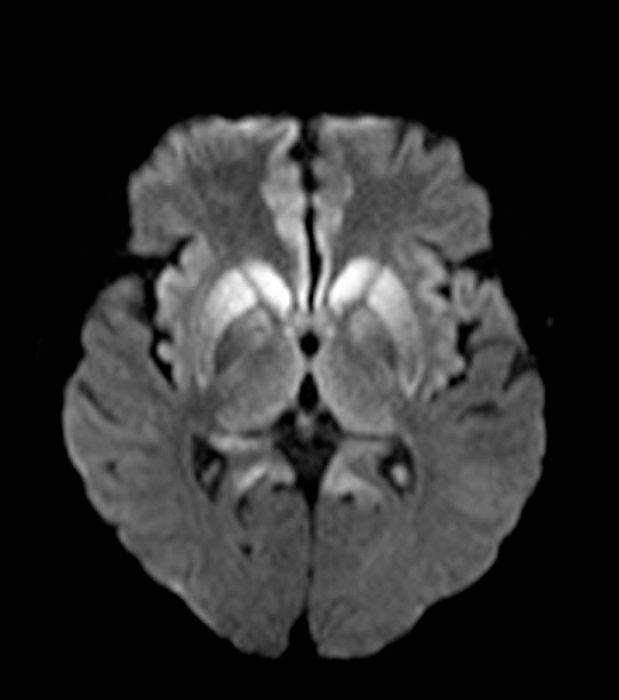

El uso de resonancia magnética (RM) en pacientes que presentan síntomas compatibles con la enfermedad aumenta la sensibilidad del diagnóstico hasta el 98%4. Los hallazgos característicos en esta consisten en hiperintensidad de la corteza cerebral y/o núcleos de la base, especialmente caudado y putamen. También se ha descrito el signo del pulvinar, que consiste en un aumento de señal simétrico en ambos núcleos pulvinares del tálamo con respecto a la corteza cerebral y la parte anterior del putamen; sin embargo, se pueden presentar falsos positivos. Otro signo descrito es el signo del “palo de hockey”, en el cual se observa un compromiso de los núcleos dorsomediales y pulvinares del tálamo3,4,5,6,7.

Se llegó al diagnóstico gracias a los hallazgos imagenológicos donde se pueden detallar los signos más comunes encontrados y descritos de la enfermedad en la literatura (hiperintensidad de los núcleos de la base, restricción a la difusión de los núcleos de la base, la corteza frontal y el giro del cíngulo y signo del “palo de hockey”) (Figs. 1,2y3), que junto con la clínica de la paciente y hallazgos en el EEG permitieron realizar el diagnóstico de ECJ.

En nuestro caso, los principales criterios diagnósticos fueron: el deterioro neurológico rápidamente progresivo, dos manifestaciones clínicas (mioclonías, compromiso de la vía piramidal), hallazgos típicos del EEG y de la RM cerebral, tratándose entonces de un caso probable de la enfermedad. Dentro de los diagnósticos diferenciales por RM están: enfermedad de Gerst mann-Sträussler-Scheinker2, encefalitis autoinmune, desmielinización osmótica, lesión cerebral hipóxica/ anóxica, encefalopatía hepática, encefalopatía hipoglucémica y enfermedad mitocondrial.